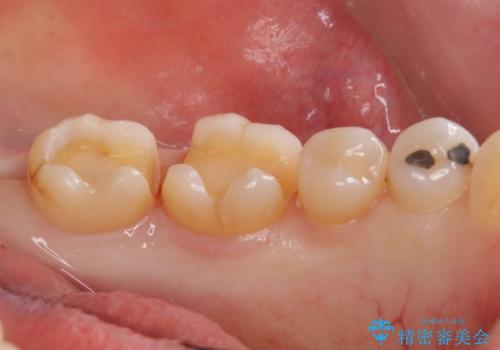

アマルガムを除去 虫歯を除去して、セラミックのつめものに

- 劣化したプラスチックとアマルガムをはずしてセラミックにしていく治療を行いました。

①初回 アマルガム、古い詰め物の除去、虫歯の除去

裏打ちをしく、インレーの形として整える、シリコンを使用した歯型とり

仮の詰め物でお帰り頂きます。